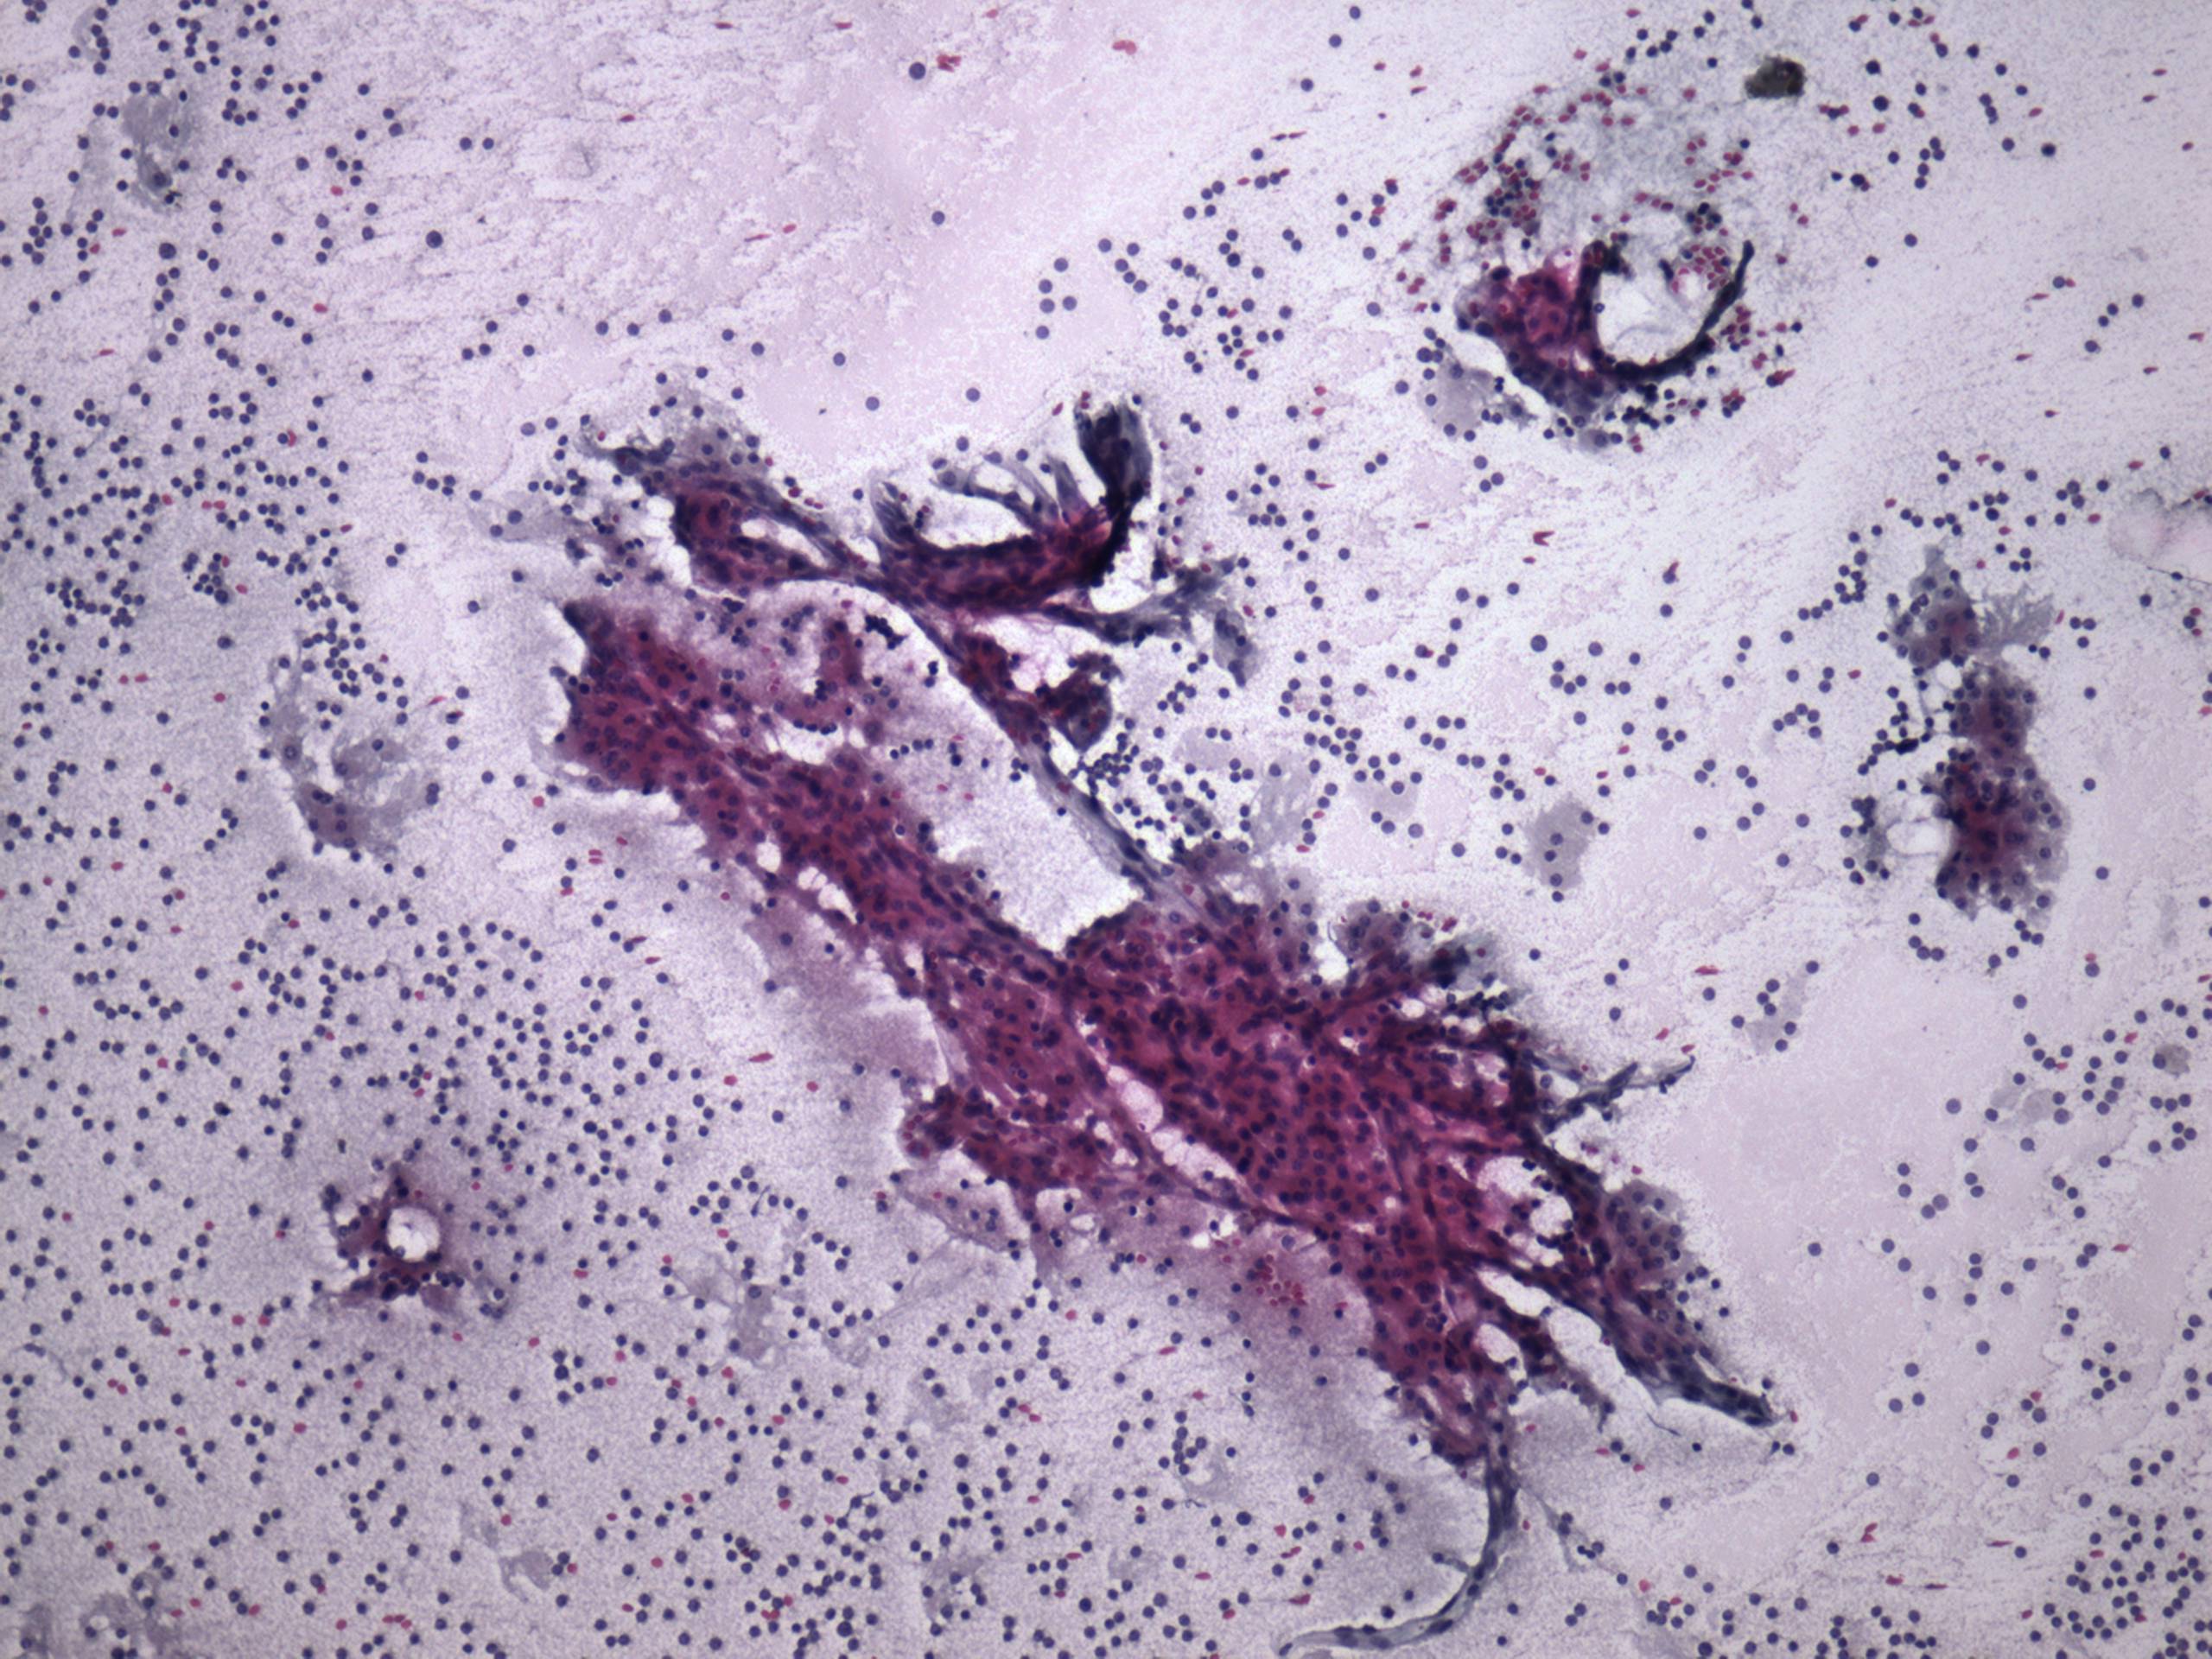

Pap-smear, 100x. A very cellular pattern. Epithelial cells occur dispersed in monolayered sheets.